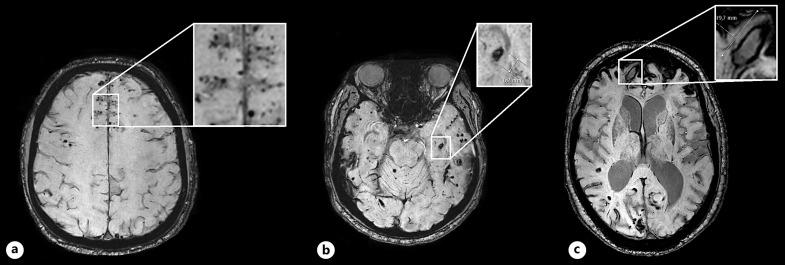

MRI rating criteria for small vessel disease markers include definitions for microbleeds and macrobleeds but do not account for small (<10 mm) hemorrhages with a cystic cavity and/or irregular shape. Such hemorrhages, however, are often present in patients with cerebral amyloid angiopathy (CAA). In this study, we aimed to investigate the frequency, diameter, and volume distribution of these hemorrhages (which we called mesobleeds) in patients with CAA.

We included 25 participants with D-CAA (mean age 56 years) and 25 with sCAA (mean age 73 years). In total, 11,007 microbleeds, 602 mesobleeds, and 195 macrobleeds were observed. Eighty-two percent of participants had ≥1 mesobleed. Hemorrhage diameter and volume were calculated in four participants with 272 microbleeds (median diameter 1.52 mm, volume 0.004 mL), 84 mesobleeds (median diameter 5.61 mm, volume 0.06 mL), and 37 macrobleeds (median diameter 19.58 mm, volume 1.33 mL). Mesobleed diameter and volume were larger than microbleeds (optimal cut-off 0.02 mL) but showed overlap with macrobleeds.

Hemorrhages <10 mm with an irregular shape and/or cystic cavity are frequently found in participants with CAA and have a distinct diameter and volume distribution. We propose to name these hemorrhage mesobleeds and to rate them separately from micro- and macrobleeds. Future research is necessary to investigate their pathophysiology and prognostic value.